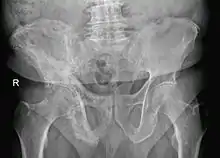

Elle est caractérisée par l'hypertrophie et la déformation de certaines pièces osseuses, principalement le bassin (près des 3/4 des atteintes), le crâne (40 % des atteintes), le rachis lombaire (près de la moitié des atteintes) et les os longs[4]. On peut retrouver des signes vasomoteurs, tels qu'une chaleur, une rougeur de la peau sus-jacente.

L'aspect radiologique est typique avec une déformation des os comprenant des zones déminéralisées et des zones de condensation.